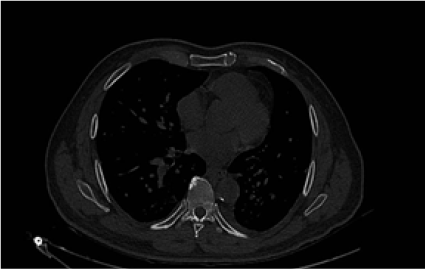

Radiográficamente, se evidenció radioopacidad en lóbulo superior izquierdo que desplaza ipsilateralmente el bronquio principal izquierdo, con criterios de atelectasia lobar superior izquierda (Figura 3). La tomografía resaltó interrupción abrupta del bronquio del lóbulo superior izquierdo asociado a lesión de 3,7 x 3,2 cm que condiciona atelectasia del lóbulo superior izquierdo en relación con proceso neoformativo (Figura 4), nódulos pulmonares de distribución aleatoria, adenopatías cervicales, mediastínicas y retroperitoneales, también lesiones nodulares hepáticas y una lesión que realza con contraste en riñón derecho. Se identificaron adenopatías en los niveles II, III y IV derecho y II, III , IV izquierdo. Adicional lesiones de densidad intermedia en el riñón derecho que realzan en la fase contratada (Figura 5A). Lesiones blásticas con probable relación con depósitos secundarios en T5, T10, T11, L3 Y L5 (Figura 5B). Biopsia de la lesión es positiva para adenocarcinoma pulmonar con patrón histológico tipo acinar. Se identificó deleción del exón 19 de receptor del factor de crecimiento epidérmico (EGFR).

Figura 4.

Interrupción abrupta del bronquio del lóbulo superior izquierdo asociado a lesión descrita que condiciona atelectasia del lóbulo superior izquierdo en relación con proceso neoformativo.

Fuente: Servicio de Radiología, Complejo Hospitalario Arnulfo Arias Madrid